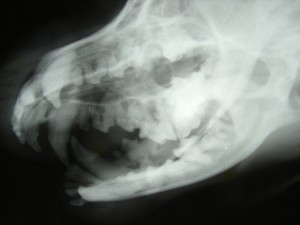

Digital dental radiology helps us see what the naked eye can't. While an oral exam can evaluate the visible surfaces of the teeth and gums, dental X-rays provide a view of what's happening below the gumline and within the jaw.

This deeper look helps our veterinarians detect, assess, and prevent dental problems that can otherwise go unnoticed.